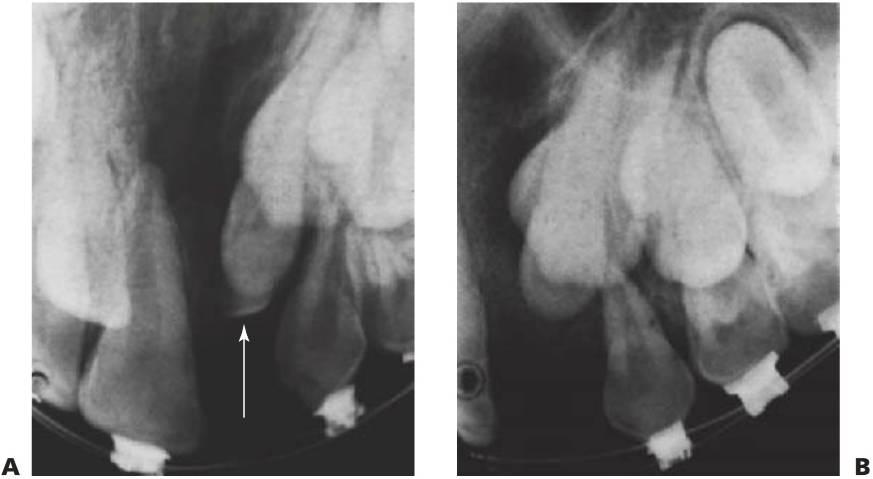

Pueden existir hendiduras labiales y leporinas de expansión variable y en un gran número de combinaciones. En las hendiduras completas existe una comunicación directa entre las cavidades oral y nasal en el lado de la hendidura (fig. 12.1 A) y el grado de separación de la placa palatina puede ser muy variable.

La hendidura puede ser simétrica o asimétrica. En las hendiduras labiales y palatinas completas bilaterales, ambas cámaras nasales se comunican de forma directa con la cavidad oral. Los procesos palatinos están divididos en dos partes iguales y los cornetes se muestran claramente visibles en ambas cavidades nasales. El tabique nasal forma una estructura en la línea media anclada firmemente a la base del cráneo, si bien aparece bastante móvil en su parte anterior, la que soporta el premaxilar y la columela (fig. 12.1 B).

La mitad labial del segmento medial contiene sólo tejido conjuntivo colagenoso y es la razón por la que su volumen está muy mermado y carece de las características que suele aportar el músculo (fig. 12.1C).